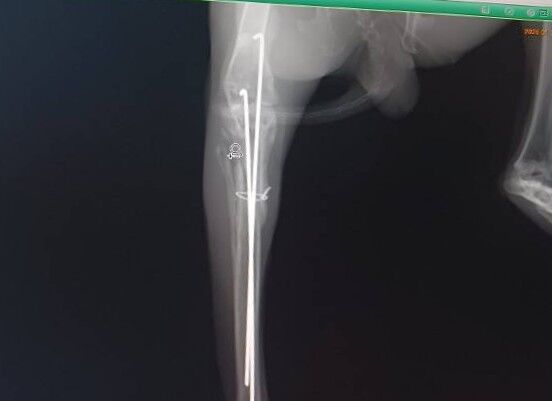

2025年11月に右後ろ脚を骨折し、11/14にピンニング手術を受け、現在も経過観察中です。

1/10 経過の診察を受けました。

足の曲げ伸ばしや太ももの筋肉の状態は良好で、まだ力は弱いものの、自分の足で押し返そうとする反応が見られました。

レントゲンでは骨の形成は概ね順調でしたが、固定していたピンのうち1本が抜けてきていることが確認されました。

このため、早めにピンを抜去する方針となりました。

1/14 ピン抜去手術

予定通り2本のピンを抜去し、手術は大きな問題なく終了しました。

足の可動は保たれているものの、レントゲン上では膝の骨がやや前方に出ており、過去に靭帯を損傷していた可能性があるとの説明を受けました。

将来的に関節への負担が出る可能性はありますが、現時点では慎重に経過を見ていくことになりました。

術後は運動量を制限し、内服薬を使用しながら回復を待ちます。

1/20 抜糸と経過を診ていただき、傷の状態は良好でした。

右後肢の筋肉はもう少しついてほしいものの、足裏の汚れから、少しずつしっかり使えてきている様子がうかがえます。

今後は様子を見ながら、生活スペースを徐々に広げていく予定です。

次回は2/10にレントゲン検査を行う予定です。

カラーが外れ、はるくんが少しでも快適に過ごせる時間が増えていくことを願いながら、引き続き見守っていきます。